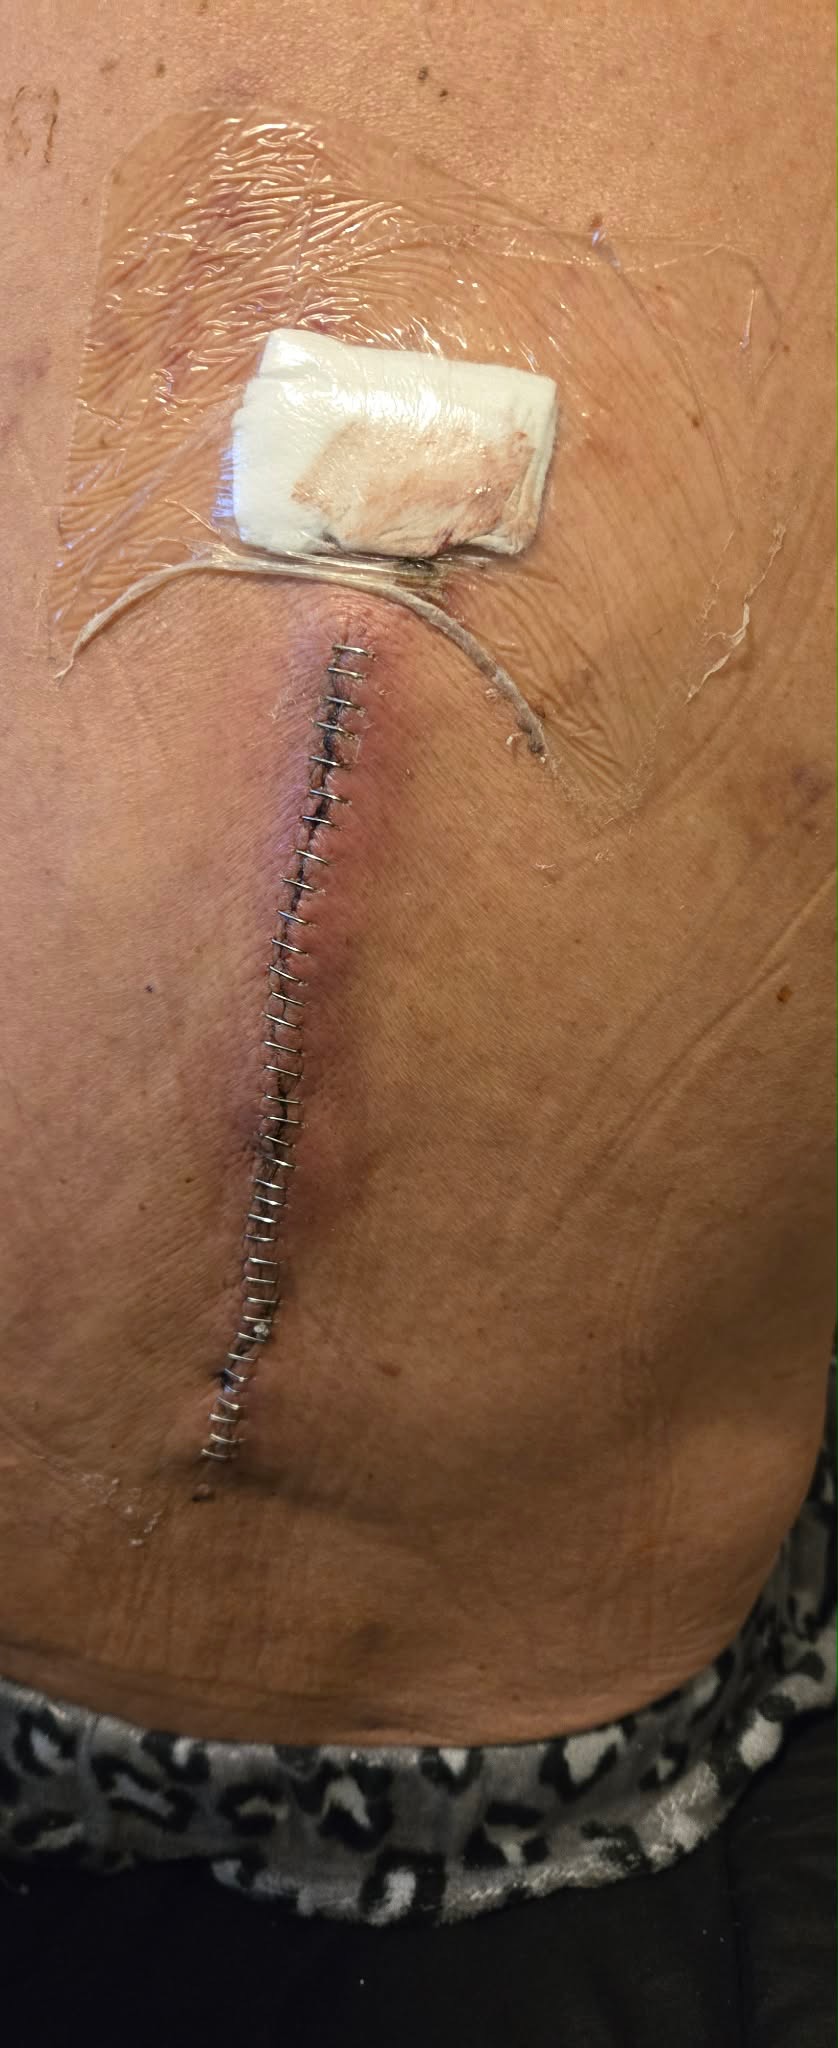

Hi everyone! I have a really good friend from work, Tina, who I’ve know for several years now. She is amazing and is always there to help and support everyone else! She is going through a tough time currently as her husband, Richard, had a work accident at the beginning of December. He was working at his construction job when a finished wall fell on top of him, landing on his head/ neck. Breaking his T12 and L1 vertebrae in his spine, as well as two other severe fractures.

He was in the hospital for 9 days and had two different surgeries during that time. Since then he has had 3 different emergency room visits and 5 doctors appointments, with 4 more coming up within the next week or so.